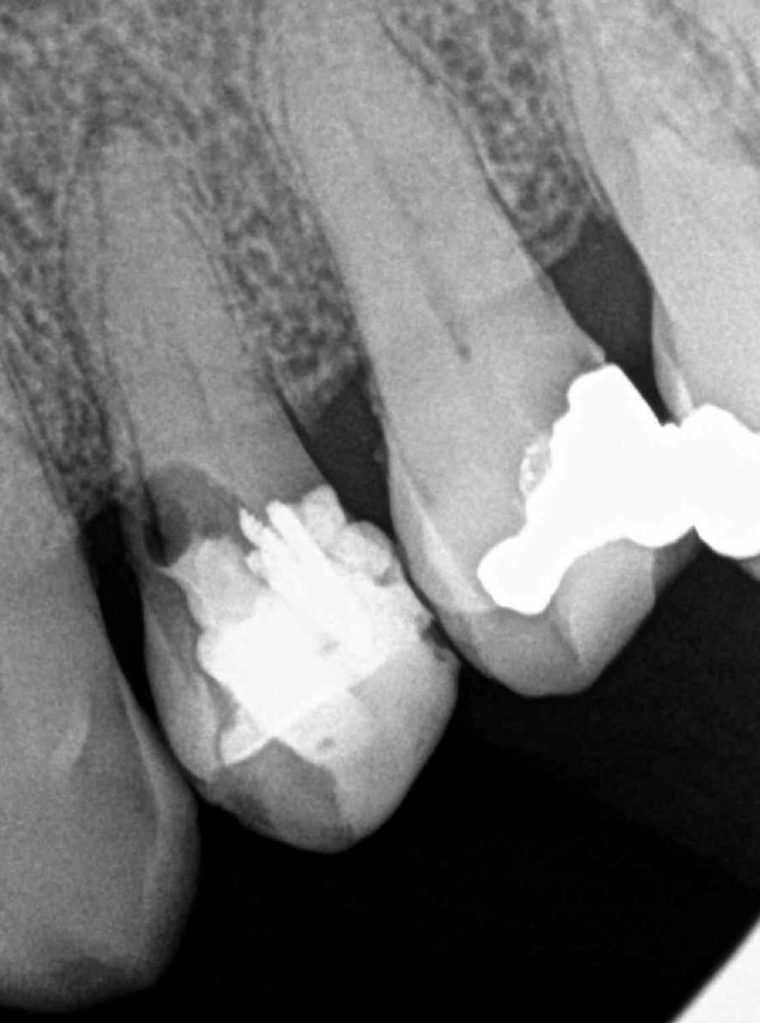

Fisura, remoción amalgama para explorar